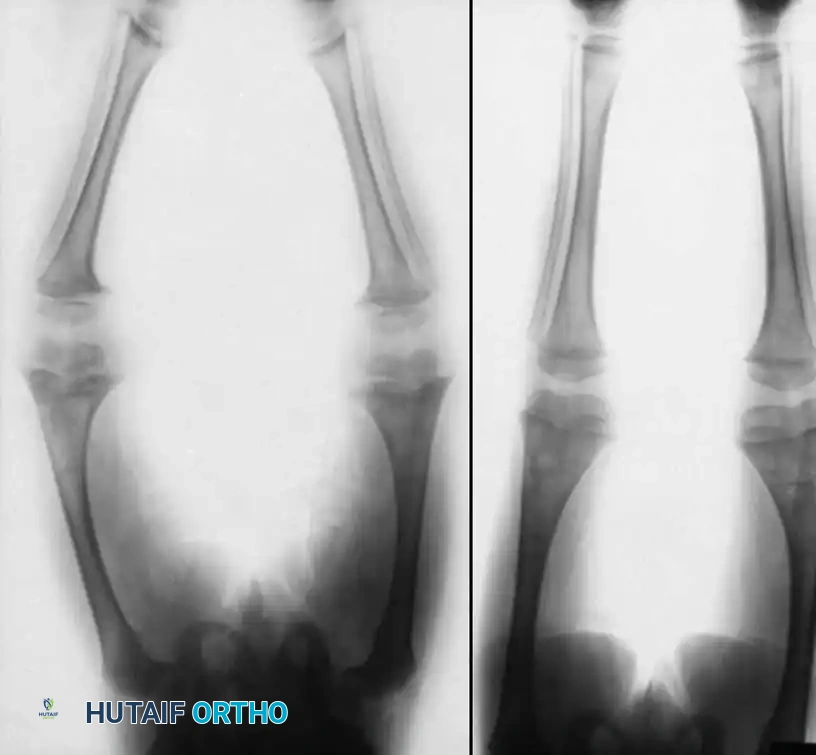

Image

Fig. 29-39 C, Two years post-osteotomy. The vitamin D–resistant rickets is now well controlled with high doses of vitamin D, calcium, and phosphorus. The mechanical axis remains corrected with no recurrence of the deformity.

Choi et al. evaluated patients with hypophosphatemic rickets undergoing knee deformity correction and leg lengthening via the Ilizarov method. While nearly all patients achieved mechanical correction, the regenerate healing indices correlated directly with biochemical parameters.

⚠️ Surgical Warning: Phosphate Levels and Regenerate Bone

If deformity correction is to be combined with distraction osteogenesis (leg lengthening), the serum phosphate level must be maintained at > 2.5 mg/dL. Patients with serum phosphate levels below this threshold exhibit severely delayed regenerate consolidation, risking nonunion, regenerate collapse, or hardware failure.

Diagram illustrating the stages of regenerate bone healing (I through VI) following osteotomy. Rapid progression through these stages in metabolic bone disease is entirely dependent on maintaining serum phosphate levels > 2.5 mg/dL.